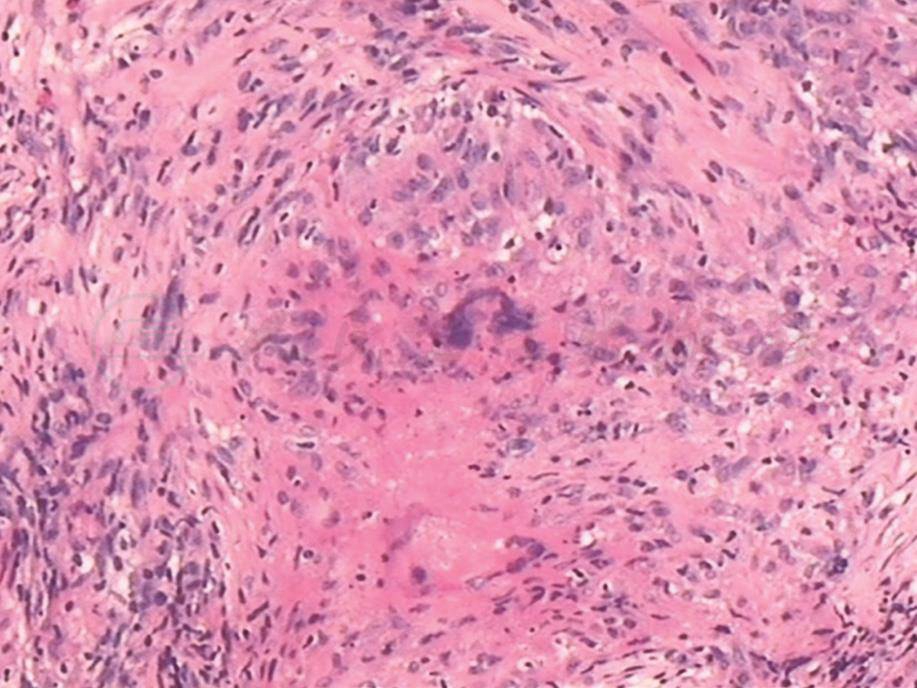

胸膜活检病理结果显示干酪性肉芽肿改变(图10),颈部淋巴结活检可见非干酪性肉芽肿改变(图11),考虑为结节病。

图10 胸膜活检病理表现

胸膜活检病理结果提示类上皮细胞肉芽肿伴多核巨细胞及中心凝固性坏死,符合结核病表现(HE染色,400×)

引自:呼吸系统疑难病例诊疗辨析.第1版.ISBN:978-7-117-26415-0.主编: